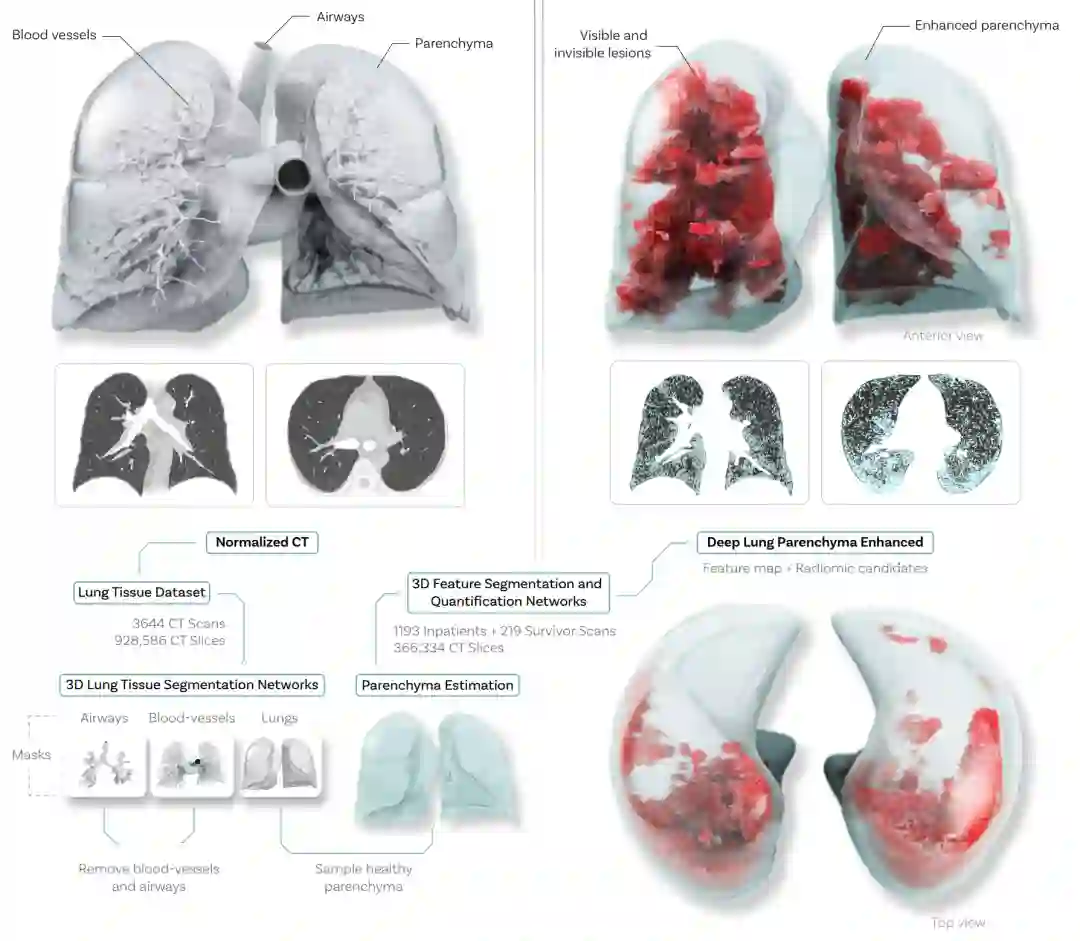

量化肉眼不可见的肺损伤分为两大步骤。第一步是把这些肉眼不可见的损伤用可解释的方式展现给医疗专家,第二步是让医疗专家标注出哪些地方是损伤,并训练模型去自动量化这些肺损伤。下图展示了第一步,图中的CT来自于一个有严重呼吸后遗症的新冠幸存者:左边是原始的CT,肉眼看和正常人无异,右边是用机器学习模型增强后的,能看到大范围的纤维化病变。原始CT看不到这些肺损伤,是因为CT信号取值范围极宽(-1000到3000),而这些肺损伤的CT信号和健康肺组织差异很小(平均约25);另外肺部的气管、血管等组织因为很强的CT信号值也会较大程度上干扰对肺损伤的观察。因此,为了能让医学专家看清这些肺损伤,高欣课题组首先训练了各种肺组织分割模型,去除了血管,气管等无关组织,然后统计肺内CT值为每个病人自动地计算了观察肺损伤最优的信号区间:例如患者A最佳的观察范围是CT信号 -720 到 -800,患者B最佳观察范围是CT信号 -650 到 -740。这样肺损伤就清晰了十几倍,得到了下图右边的样子。第二步,医学专家给肺损伤进行标注,作者们利用标注实现了对这些肺损伤的自动分割和量化,量化得到了6个肺损伤指标。作者将这一套流程简称为DLPE。

DLPE模型的成功不仅在于它流程的新颖性,更在于它实现了最优秀的血管分割和气管分割。气管和血管具有自相似性,作者证明了小血管、小气管的体积是极小的:占据总长度50%的最细的气管(血管)仅仅占据总体积的6.60%和6.11%。因此,用传统的损失函数,比如dice loss,cross-entropy loss等,模型无需分割小血管、小气管,就已经收敛了。为了解决这个问题,作者提出了feature-enhanced loss,其核心思想是让每一级血管(气管)得到相同的“关注”:每一级血管(气管)总和的loss weight是相同的。这样,DLPE实现了对小气管、小血管的精确分割。为了解决DLPE的泛化能力,作者提出了two-stage segmentation protocol:第一个阶段确定气管和血管的大体位置,将搜索空间缩小了上千倍;第二个阶段得到最后的血管和气管分割。这样,DLPE可以在各种不同的数据上进行稳定的预测。

DLPE有着可解释的流程。其中的分割模型是基于2.5D模型:训练的时候刻意隐藏了3D长程结构特征,预测时通过长程结构的重构来检验预测结果是否正确。对于肺损伤的增强、radiomics的量化,则是用传统算法(非深度学习)。